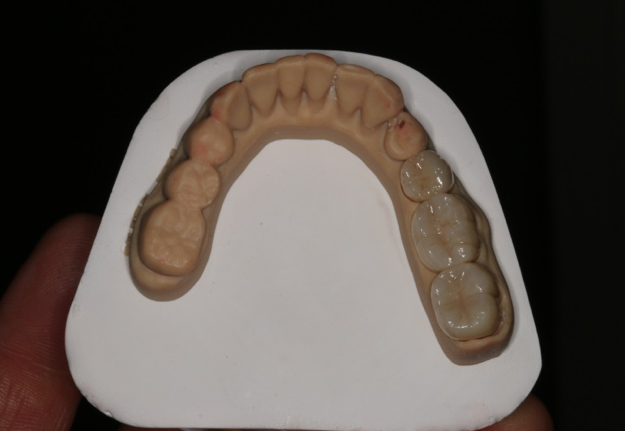

Fig 3. 3D-printed model.

Figure 3

After completing an initial diagnostic appointment, a patient accepted three single-unit full-contour zirconia crowns that were milled from the digital impression and cut back for porcelain application. The application by a technician is analog dentistry. The ability of a dental laboratory to scan an analog crown-and-bridge impression is called converting an analog impression to a digital impression. The workflow after the conversion has become digitized. A dental model is virtually created with computer software, and a full crown proposal is fabricated for inspection virtually before the crown is milled (Figure 2). Due to the color of the digitized impression, the margins of the crown preparations are more easily and rapidly identified. The laboratory will also 3D print a working model, which will be used to develop the morphology of the final restoration by hand placement of porcelain (Figure 3). The decision to prescribe a full contour zirconia crown with cutback for porcelain application or complete full contour zirconia crowns lies solely on the attending dentist.9 A discussion with the patient before preparation of the teeth is imperative. After the discussion, the patient requested the zirconia copings with cutback and porcelain application for the posterior crowns (Figure 4 and Figure 5).